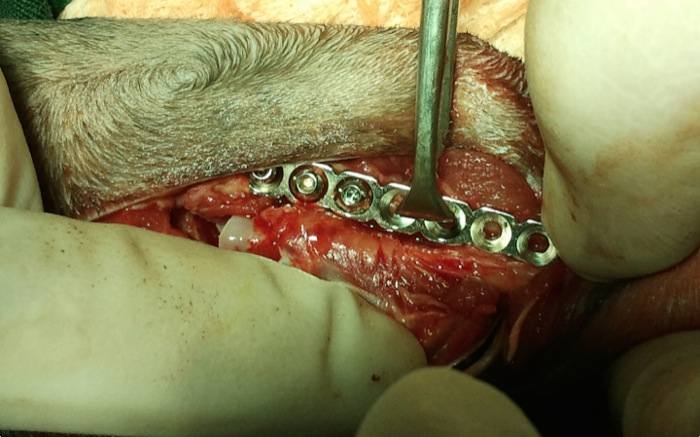

Estamos frente a una explosión del codo y esperábamos múltiples lesiones que no vemos en una placa: rotura de ligamentos, cápsula, tendones y músculos adyacentes y fisuras. Vemos la lesión de codo donde bajo piel y subcutáneo intactos encontramos un grupo de fragmentos y superficies articulares. Destaca en el margen superior el ligamento anular del radio.

Empezamos reconstruyendo la articulación con manipulaciones precisas para no fragmentar ninguna de las partes. Se elige una placa de reconstrucción para adaptarse a cualquier pequeña curvatura del hueso.

La inestabilidad es completa aún entre los 3 huesos de la articulación.

En este caso aplicamos tornillos de 1,5 mm que entran en lateral al cúbito. Con 2 tornillos, en cabeza de radio uno y otro en cóndilo humeral, y una sutura no absorbible (Premicrom® 2/0) tenemos una prótesis que mantendrá radio y húmero en posición fisiológica.